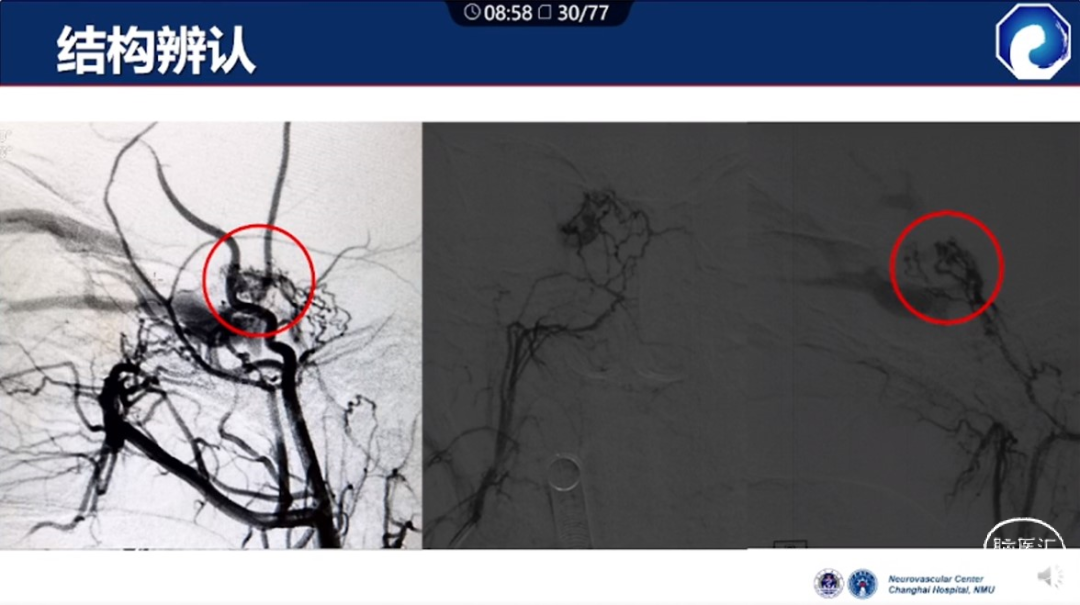

痿口静脉端的识别至关重要。

痿口静脉端精准完全闭塞是DAVF治愈的关键。

减少栓塞材料应用。

减少与颈内动脉重叠,避免栓塞材料意外栓塞。